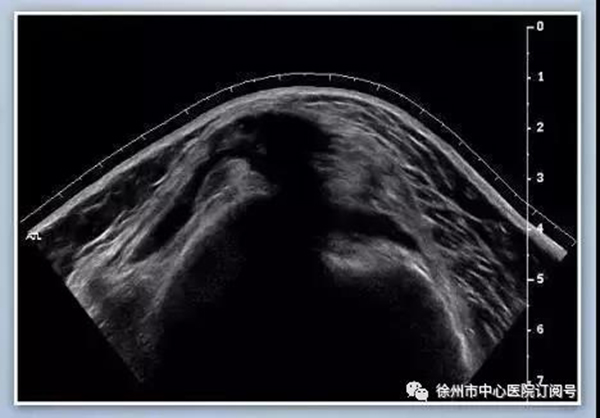

肌骨超聲是指使用高頻超聲(5-13MHz)診斷人體軟組織、肌腱、神經(jīng)、骨骼和關(guān)節(jié)病變的一種超聲檢查方法。肌肉-骨骼系統(tǒng)超聲能夠提供更細(xì)微的軟組織分辨率,是能夠顯示肌腱和神經(jīng)等結(jié)構(gòu)的重要影像手段,在診斷關(guān)節(jié)、肌肉、肌腱、韌帶、筋膜、滑膜及周圍神經(jīng)疾病中有不可替代的作用。

肩部疼痛治療方法以往通常采用物理療法和藥物治療,當(dāng)疼痛明顯,肩關(guān)節(jié)粘連(凍結(jié)肩),一些常規(guī)方法不能很快緩解的情況下,選擇神經(jīng)阻滯和關(guān)節(jié)腔囊內(nèi)注射是有效的治療方法,超聲作為該治療方法下的輔助工具是一種非常靈活的臨床檢查,安全無(wú)輻射,顯著提高穿刺的成功率和療效,減少并發(fā)癥,在慢性疼痛治療中已被臨床醫(yī)生和患者廣泛接受。超聲引導(dǎo)下慢性肩周圍疼痛注射是介于保守治療與手術(shù)治療之間的微創(chuàng)介入治療手段,注射部位以診斷為依據(jù),包括肩關(guān)節(jié)、相關(guān)神經(jīng)阻滯和關(guān)節(jié)囊注射。常見(jiàn)的神經(jīng)阻滯部位為肩胛上神經(jīng),而關(guān)節(jié)囊注射部位通常為肩峰下,肩鎖關(guān)節(jié)或者關(guān)節(jié)腔內(nèi)注射。